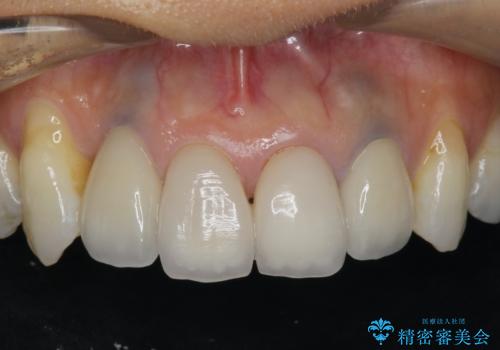

歯ぐきの黒ずみ クラウンやりかえによる改善